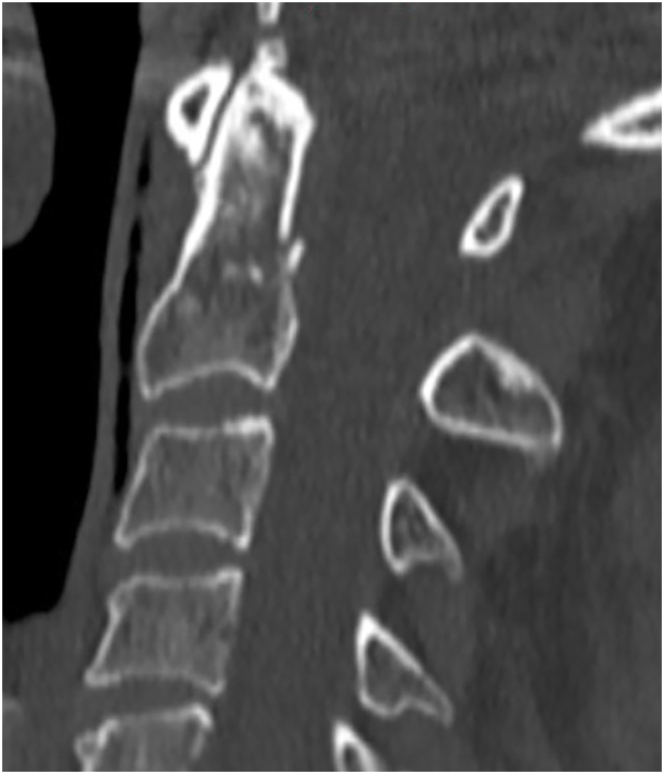

Introduction: Controversy exists regarding the optimal management of type II odontoid fractures in the geriatric population. The objective of this study was to determine the current treatment patterns of spine surgeons for geriatric patients (≥70 years) with type II odontoid fractures.

Results: A total of 154 responses were collected from 119 neurosurgeons (77.8 %) and 34 orthopedic surgeons (22.2 %). Participants were predominantly from Europe (92.7 %), and 63.2 % have been in practice >10 years. Fracture displacement, comorbidities and age were the most influential factors for decision-making. For non-displaced fractures, 78.8 % of respondents recommended conservative treatment for patients aged 70-80 years, and 83.7 % for those aged 80-90 years. For displaced fractures, 70.9 % preferred surgery for patients aged 70-80 years, whereas this preference decreased to 47.9 % for those aged 80-90 years. Posterior C1-2 fixation was the most common technique for 67.3 % of respondents, and 48.3 % prescribe a collar postoperatively. 51.3 % routinely order CT imaging postoperatively to assess for bony fusion. For conservative treatment, 59.3 % prescribe an external orthosis for 3 months.